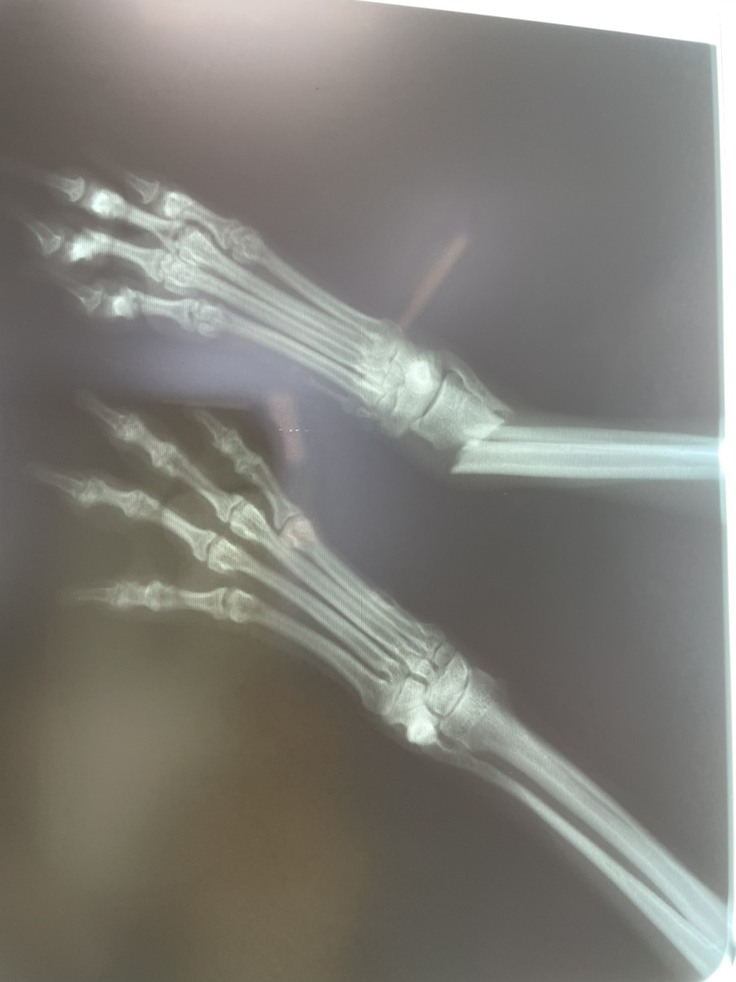

連れて来た時には右脚プラプラ。 あれ? これはもしかして…と思い、

すぐ病院へ。

案の定「骨折しています」と…。

治療・手術内容 右前足の骨折。切開をして鉄板を入れボルトで止める手術。